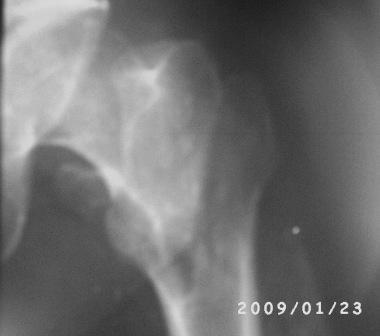

Больному 50л. В отдаленном от центра р-не ДТП 6.12.08г. д-з " тяжелая

ЧМТ, мн. переломы ребер слева, отрыв ножки селезенки, повреждение п/ж

железы, з/двойной перелом прав. бедра.После экстрен. хирургических

вмешательств, конечность фиксирован кокситной гипсовой лонгетной

повязкой. Кома 2 нед, нагноение п/о раны живота, постравмат.

пневмония.

20.01.09г. переведен к нам. Постельный больной,

ослабленный, бледный, весом 56кг:  свищ п/о раны перед.брюшной стенки

с сукровичным выделением, гипс снят - деформация и укорочение

бедра на 6см, в обл перелома есть спайка. Слабо, но активно поднимает

ногу, контрактура т/б и коленных суставов.

Имя     : PICT0012.JPG

Тип     : image/jpeg

Размер  : 10309 байтов

Описание: отсутствует

Url     : http://weborto.net:8080/pipermail/ortho/attachments/20090125/3084e8b8/attachment-0003.jpeg